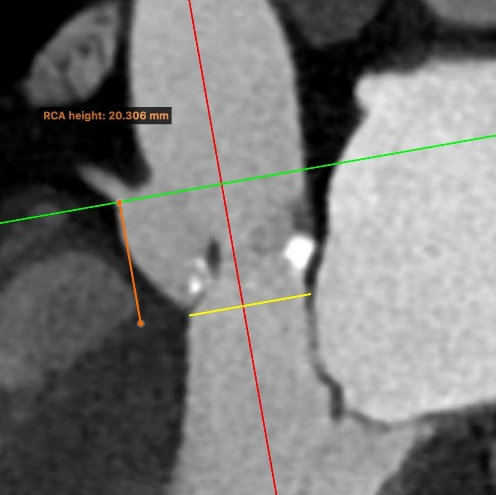

术前CT

瓣环:周长71.9mm,最大径25.6mm

法氏窦:周长109.7mm,最大径36.0mm

STJ:周长86.2mm

左冠高度:12.519mm

右冠高度:20.306mm